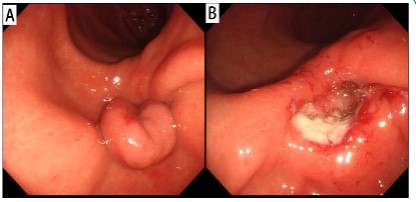

A 49-year-old man presented with a complaint of abdominal distension with decreased appetite for one month. The patient had no abdominal pain, hematemesis, melena, or other symptoms. There was no history of weight loss or family history of gastrointestinal disease. Other vital signs were normal. Abdominal physical examination showed no obvious abnormalities. Laboratory tests showed normal blood routine and tumor markers. Fecal occult blood was negative. Gastroscopy revealed a mucosal protuberous lesion in the greater curvature of the stomach, about 2.0 cm × 3.0 cm in size, extending to the pyloric canal, which was resected by high-frequency electric coil (Figure 1). The pathological diagnosis was ectopic gastroduodenal mucosa with adenomatous hyperplasia.

Figure 1: Gastroscopic images. A: Mucosal protuberous lesion in the greater curvature of the stomach. B: After resected by high-frequency electric coil.